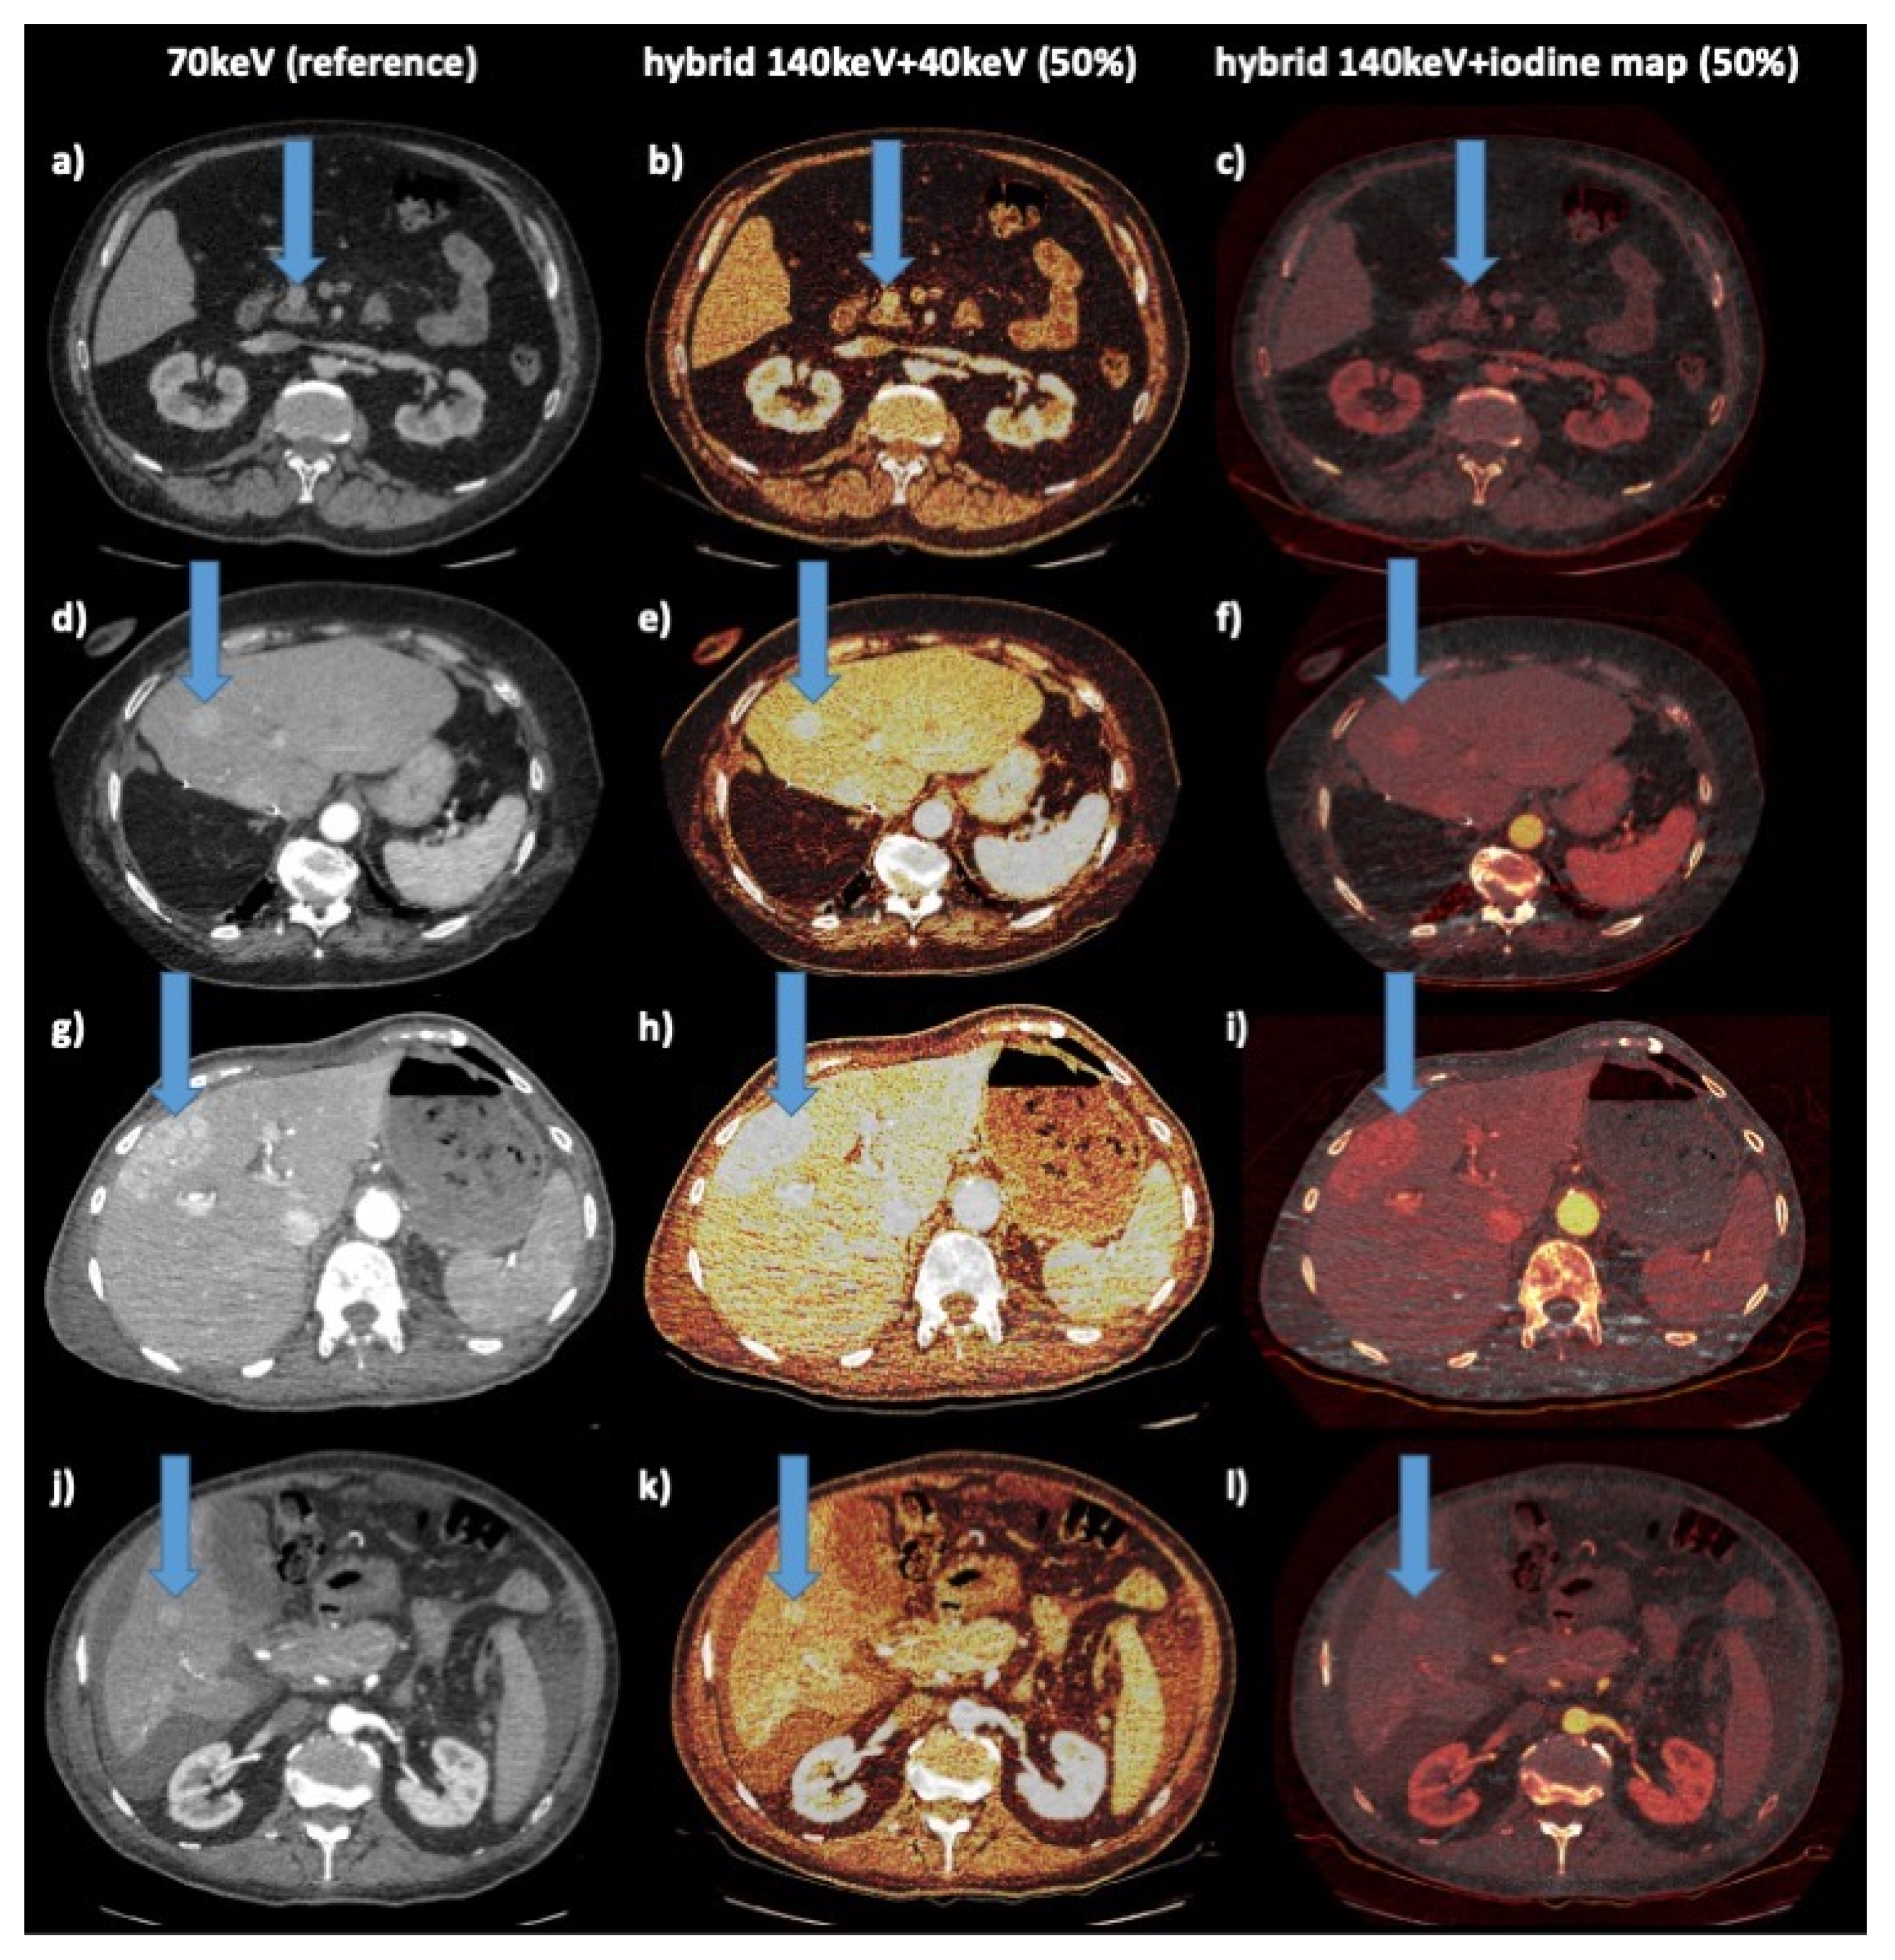

| Postprocessing datasets | 1st: 70 keV (reference) 2nd: hybrid 140 keV/40 keV (50:50 blending) 3rd: hybrid 140 keV/iodine map (50:50 blending) | Standard polychromatic images | |